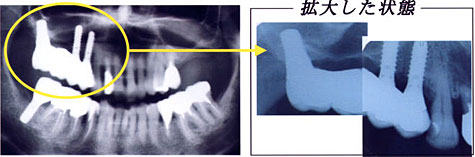

まず、『上顎結節を利用したインプラントの傾斜埋入』症例を見ていただきます。

下のレントゲン写真が治療前の状態です。

赤色の点線が上顎洞の位置で

緑色の点線が骨の外形です。

中央部には骨の高さがほとんどないことがわかります。

治療方法として サイナスリフトはせず、奥にインプラントを傾斜埋入させて行うことにしました。

同部分を拡大(抜歯前になります)したのが右側の写真です。

抜歯前の状態を見ると 骨が根の先までないのがわかります。

左のレントゲン写真が全体像で右のレントゲン写真がインプラント部分のみの拡大像です。